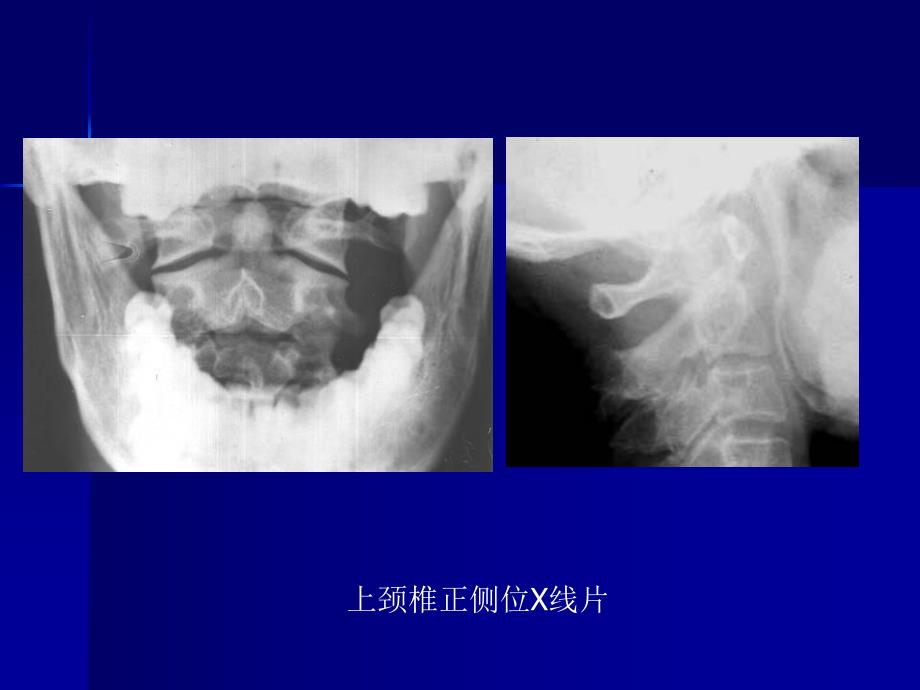

上颈椎正侧位X线片颈椎正侧位颈椎斜位X线片颈椎MRI寰椎枕骨化、颅底凹陷症游离齿突畸形C12半脱位伴颈椎椎管内占位类风湿关节炎导致C12半脱位脊髓空洞症颈椎分节不全伴脊髓型颈椎病脊髓型颈椎病脊髓型颈椎病OPLLHangman骨折颈椎骨折胸椎黄韧带骨化症颈椎损伤致颈髓T2加权高信号胸椎黄韧带骨化症LDHLDHL23结核腰3椎体骨折腰45滑脱胸2半椎体畸形腰3椎体血管瘤腰椎椎管造影L1椎体转移性肿瘤Cobbs角测量脊柱旋转程度分级椎体角和椎间盘角咽后间隙和气管后间隙椎体间活动度测量颈椎椎管矢状径测量